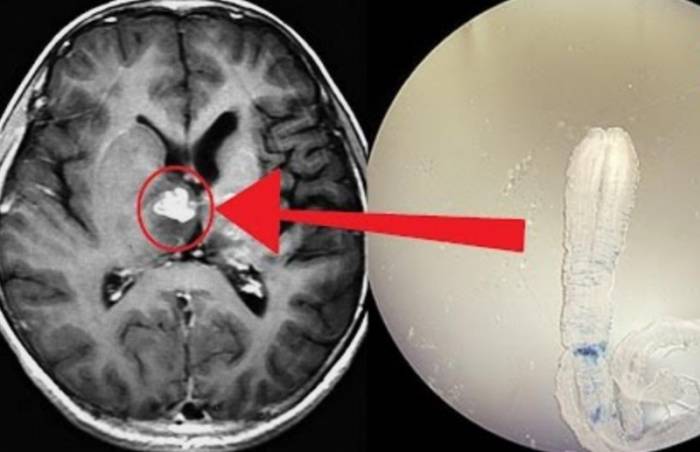

Понять, есть ли паразиты в голове человека одна из нелегких задач. Более точно можно установить диагноз используя рентгенографическую аппаратуру. Благодаря диагностике всего тела определяются пути продвижения червя.

Диагностируется наличие эхинококков в голове с помощью рентгеновских снимков. Он поможет увидеть их скопление в черепной коробке.

Диагностика может включать в себя различные методы, такие как магнитно-резонансная томография (МРТ), компьютерная томография (КТ), а также анализы крови и спинномозговой жидкости. Врач может также провести нейропсихологическое тестирование для оценки когнитивных функций.